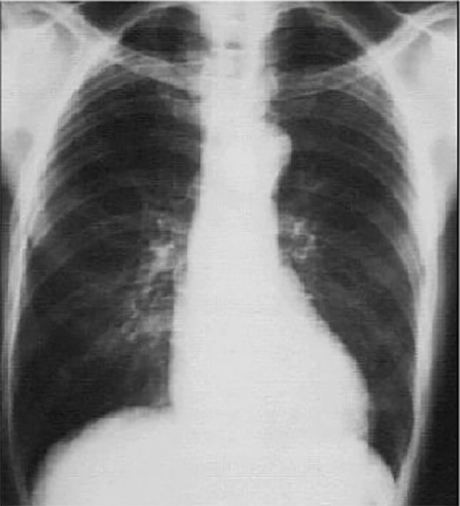

Our Patient's PA

Click on the xray to enlarge it.

Choose the best interpretation of the chest X ray:

Left ventricular enlargement

and left atrial enlargement

Prominent aortic knob

Rib notching

Dilated ascending aorta

Left ventricular enlargement and a dilated aorta